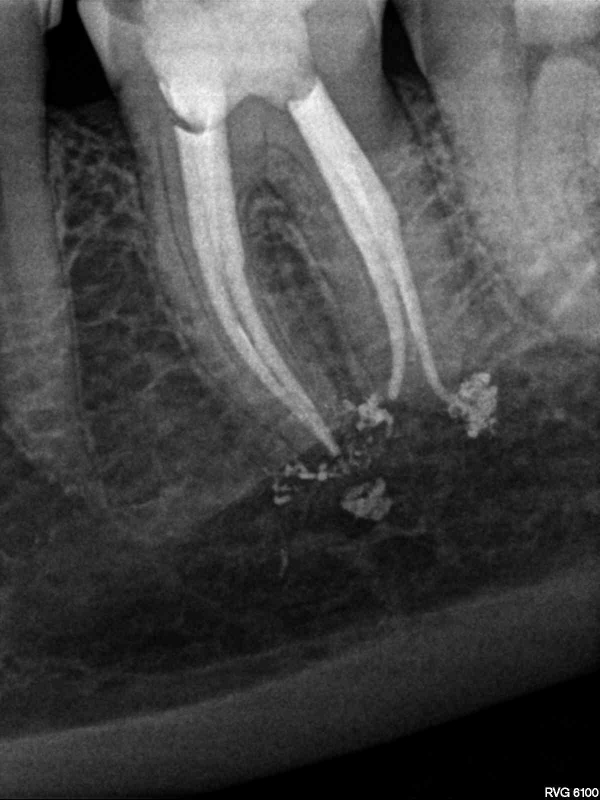

Анатомия: Межкорневая костная перегородка

Раздел: Галерея впечатлений